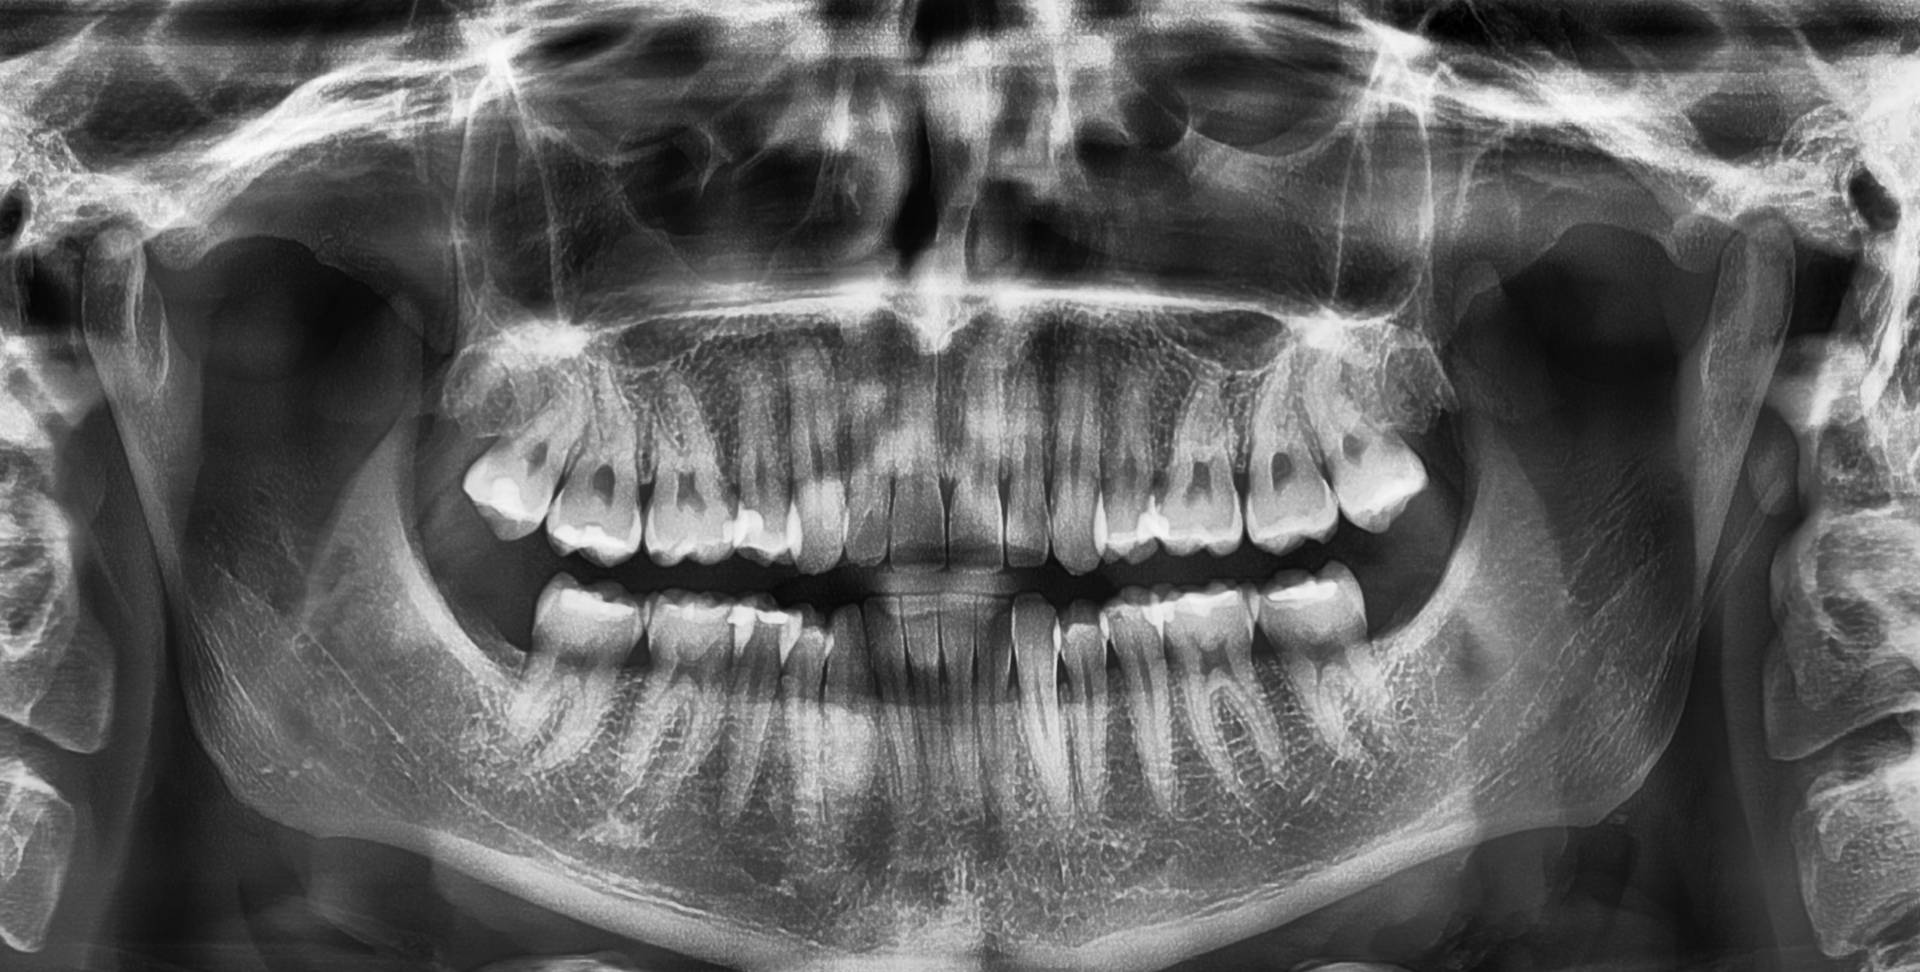

Пантомограма

Пантомограма, або панорамна рентгенографія зубів чи панорамний знімок зубів, — це метод діагностики, який дозволяє отримати зображення всієї ротової порожнини на одному знімку. Це включає верхню та нижню щелепи, зуби та навколишні структури. Вона відрізняється від стандартного рентгену зубів, який фокусується на окремих зубах. Томограф обертається навколо голови пацієнта для отримання зображення.

Панорамна рентгенографія використовується для різних цілей, таких як:

- Оцінка стану зубів мудрості (їх положення та розвиток).

- Виявлення проблем із щелепами.

- Планування дентальних імплантатів.

- Виявлення кіст, пухлин або інших аномалій у щелепній ділянці.

- Огляд носової області, верхньощелепних пазух, скронево-нижньощелепних суглобів та нижньої щелепи.

Це важливий діагностичний інструмент як у стоматології, так і в ортодонтії.